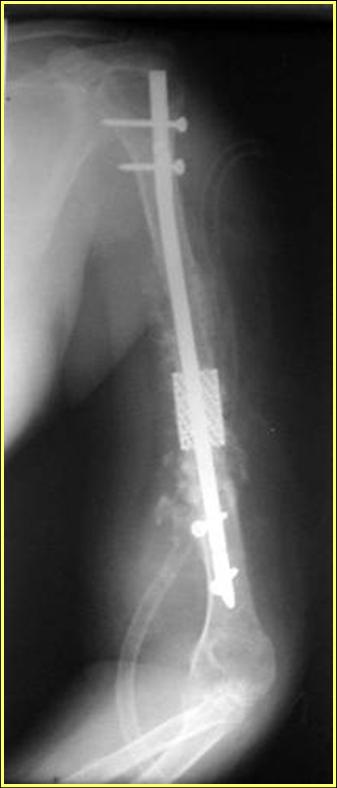

Типичная положительная ситуация для интрамедуллярного остеосинтеза с

использованием опорного металлокаркаса для компенсации дефекта.

Рентгеновская версия реконструкции. хронология:

после операции, 2 мес. после операции, через 1 год

Движения в полном объеме восстановлены к 2 мес. после операции. Если надо могу показать мультик. Сейчас уже прошло более 3 лет, больная не